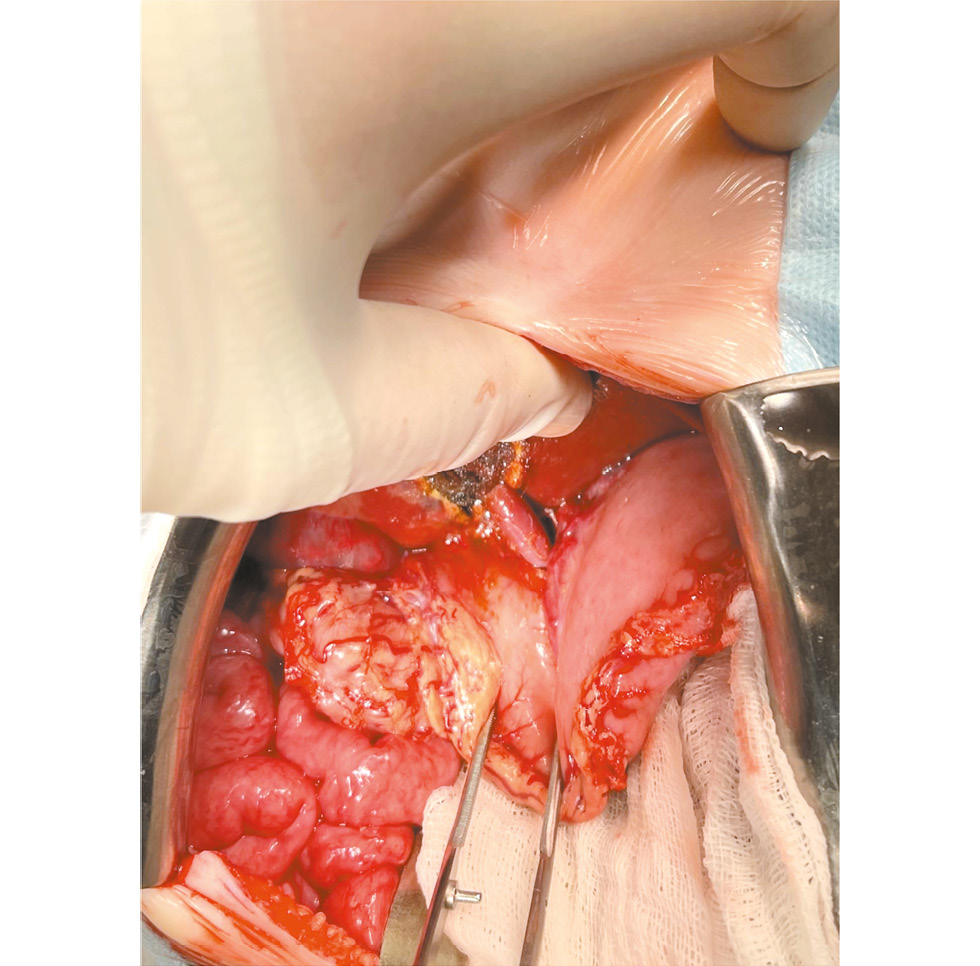

При проведении трансартериальной мезентерикопортографии также выявлены ангиографические признаки портальной гипертензии: кавернозная трансформация воротной вены, интенсивный сброс крови в расширенные вены пищевода и желудка (рис. 1).

Рис. 1. Предоперационная трансартериальная мезентерикопортография

Fig. 1. Preoperative transarterial mesentericoportography.